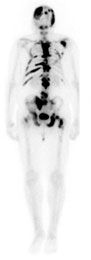

Another study, involving alpharadin, a particle-emitting isotope of radium, also reported encouraging results. This ongoing phase III clinical trial included 922 patients with both castration-resistant prostate cancer and symptomatic bone metastases. The interim analysis showed that patients taking alpharadin had a median survival of 14 months compared to 11.2 months in patients receiving the placebo.